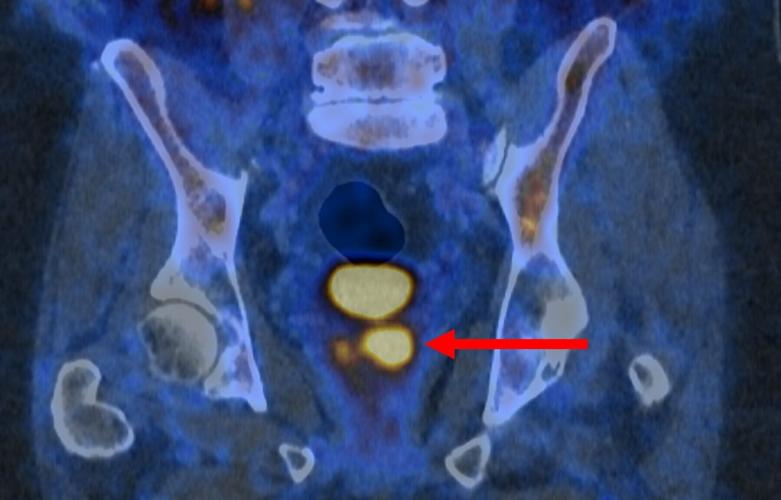

Glowing prostate cancer cells PSMA PET 2. (PRIMARY 2 via SWNS)

kAm%96 !$|p !t%^r% D42? :56?E:7:6D >@C6 288C6DD:G6 k2 9C67lQ9EEADi^^E2=<6C]?6HD^a_ad^`_^_g^?6H\5CF8\4@>3@\D9@HD\AC@>:D6\7@C\AC@DE2E6\42?46C\A2E:6?ED^Q E2C86ElQ03=2?<Q C6=lQ?@C676CC6C ?@@A6?6CQmAC@DE2E6 42?46Ck^2m 46==D[ H9:49 2C6 A@E6?E:2==J 92C>7F= 2?5 >2J ?665 EC62E>6?E]k^Am

kAmxE 5@6D D@ H:E9 2 >@=64F=6 E92E 3:?5D E@ AC@DE2E6 42?46C 46==D 2?5 42FD6D E96> E@ Q=:89E FA :? 2 C6>2C<23=6 H2JQ \ 2AA62C:?8 2D 3C:89E DA@ED :? E96 D42??:?8 :>286]k^Am

kAmsC] y2>6D qFE62F[ 2 ?F4=62C >65:4:?6 A9JD:4:2? 2E E96 !6E6C |24r2==F> r2?46C r6?EC6[ D2:5i “!$|p !t%^r% D42??:?8 >2<6D AC@DE2E6 42?46C 46==D =:89E FA :? 2 C6>2C<23=6 H2J[ A2CE:4F=2C=J :? >@C6 288C6DD:G6 42?46CD]k^Am